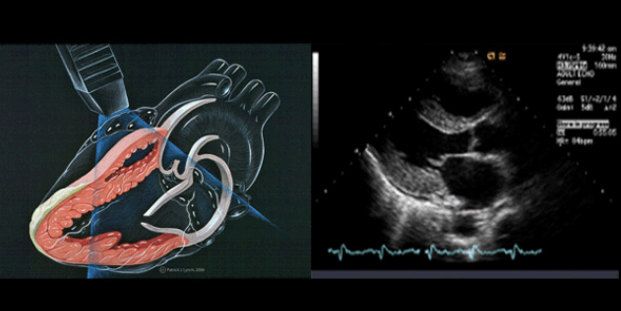

1. 심장 초음파 검사란 무엇인가?

심장초음파검사는 말 그대로

초음파를 이용하여 심장을 검사하는 것을 의미합니다.

심장초음파검사를 하는 목적은

심실의 크기 모양, 판막 움직임, 대동맥크기를 확인하여 심장구조를 검사하기 위해서 입니다.

2. 심장초음파는 어떻게 수행하는 것일까?

심장초음파도 동일하게 진행됩니다.

검사받는 사람은 몸을 왼쪽으로 돌리고 그상태에서 피부사이에 젤리를 바르고

검사를 수행합니다.

이렇게 피부사이에 젤리를 바르는 이유는

피부사이 검사장비를 매끄럽게 움직여 검사 하기 위해서 입니다.

또한 이것은 초음파의 특성때문인데, 초음파는 공기를 투과하지 못하기 떄문에

공기를 피부사이에 젤리를 통하여 공기를 제거하기 위해서라고 합니다.

아래는 심장초음파 장비 입니다.